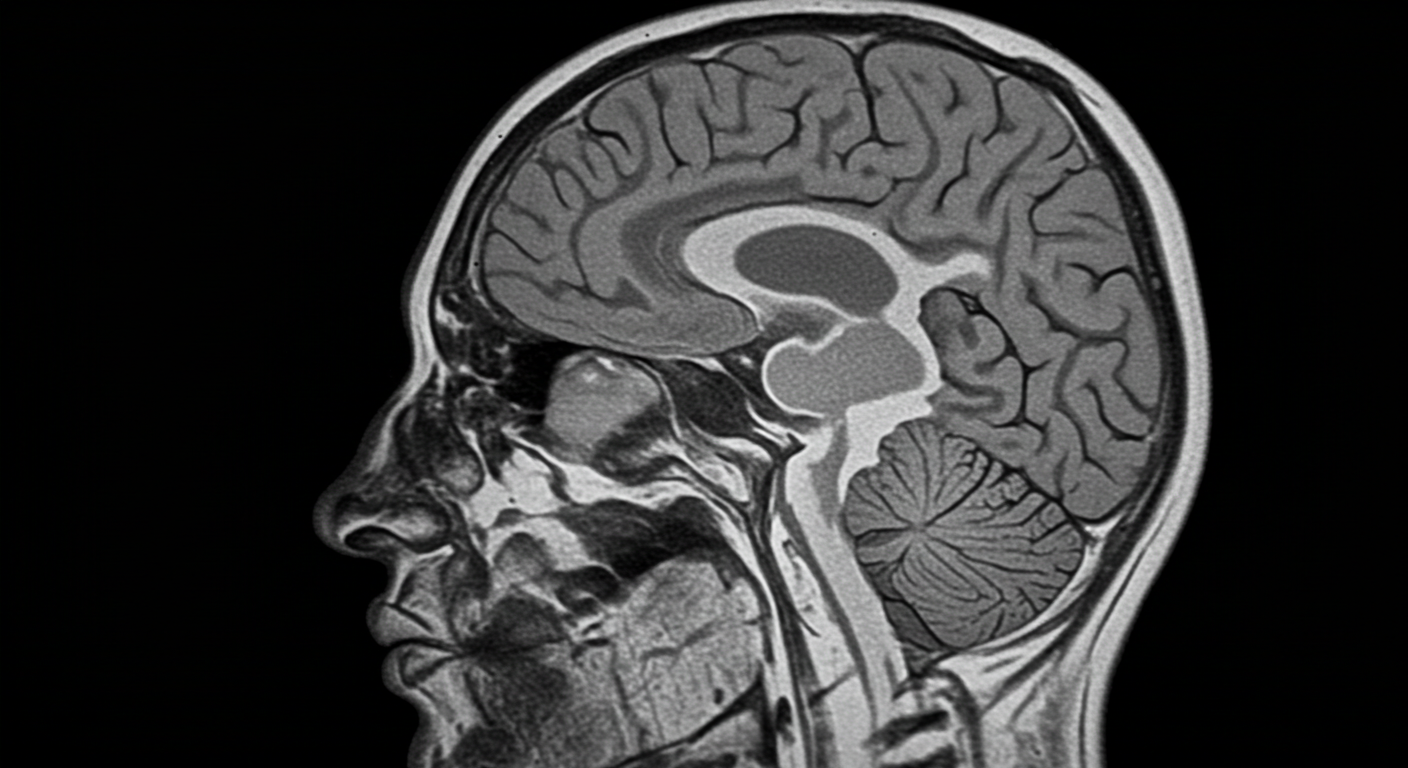

1. 뇌 MRI (자기공명영상) 검사

MR검사는 자기장과 고주파의 상호작용을 이용하여 인체의 해부학적, 병리학적인 정보를 얻을 수 있는 검사입니다. 뇌 MRI는 치매, 뇌종양 등 뇌의 구조적, 기능적 이상소견 여부를 확인하고자 하는 목적이 있습니다.

검사 특징:

- 방사선 노출 없이 뇌 구조를 상세히 관찰

- 뇌경색, 뇌출혈, 뇌종양, 치매 등 다양한 질환 진단 가능

- 검사 시간: 약 30-45분

- 조영제 사용 여부에 따라 더 정밀한 검사 가능